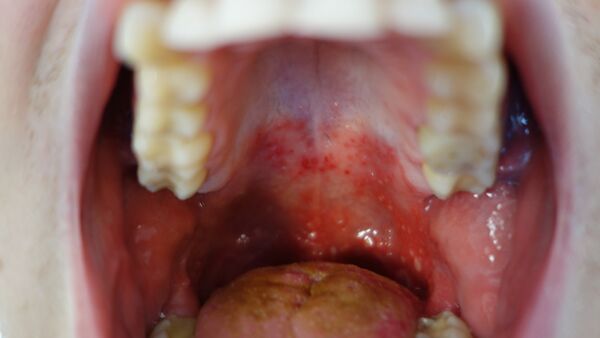

• Вирусы Коксаки типа A обычно инфицируют кожу и слизистые оболочки, вызывают острый геморрагический конъюнктивит, энтеровирусный везикулярный стоматит с экзантемой, заболевания верхних дыхательных путей и асептический менингит, миалгию[1], а также заболевания горла (герпангина).

Инкубационный период длится несколько дней. Затем у пациента наступает повышение температуры до 39—40 °С, возможны многократная рвота, диарея, появление сыпи на руках, ногах, груди и лице. Пациент ощущает головную боль, слабость. Поражается слизистая глотки, что затрудняет приём пищи. При стандартном течении болезни её симптомы исчезают за одну—две недели.